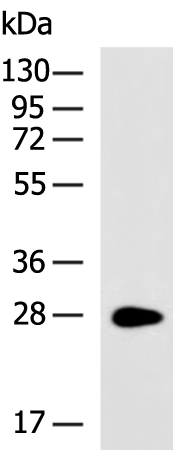

分类: 科研抗体货号: P06279别名:应用: WB,IHC反应种属: Human, Mouse, Rat

分类: 科研抗体货号: P06217别名: NEM7应用: WB,IHC反应种属: Human, Mouse, Rat

分类: 科研抗体货号: P06266别名: NCBP; Sto1; CBP80应用: WB,IHC反应种属: Human, Mouse, Rat

分类: 科研抗体货号: P06210别名:应用: WB,IHC反应种属: Human, Mouse, Rat

分类: 科研抗体货号: P06263别名: CML3; NACED; NAT8-LIKE应用: WB,IHC反应种属: Human, Mouse, Rat

分类: 科研抗体货号: P06205别名: CACC; GOB5; CACC1; CLCRG1; CaCC-1; hCLCA1; hCaCC-1应用: IHC反应种属: Human

分类: 科研抗体货号: P06262别名: DNAS1L2应用: IHC反应种属: Human, Mouse

分类: 科研抗体货号: P06203别名: BHLHF42应用: WB反应种属: Human, Mouse

分类: 科研抗体货号: P06202别名: AMY; CLAC; CLACP; CFEOM5; CLAC-P应用: WB,IHC反应种属: Human, Mouse

分类: 科研抗体货号: P06261别名: DCR2; CD264; TRUNDD; TRAILR4; TRAIL-R4应用: WB,IHC反应种属: Human